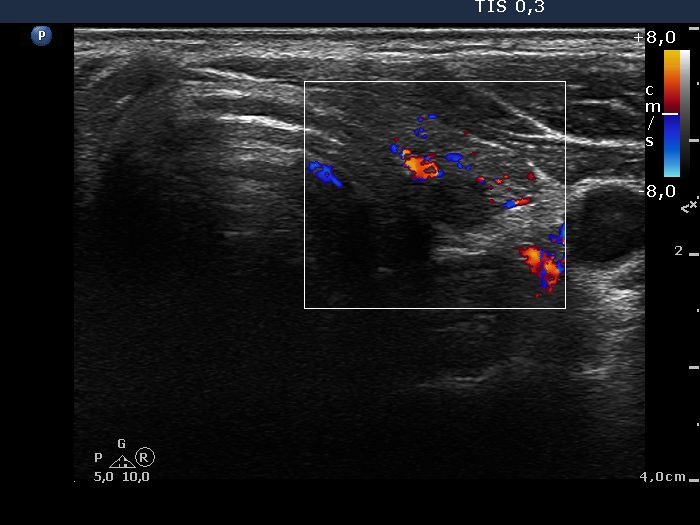

First examination (1st to 3rd rows of images):

Ultrasonography: Both lobes presented hypoechogenic ill-defined areas. The echogenicity index was 80% in the right lobe while 20% in the left thyroid. The vascularization was significantly decreased.

Elastography demonstrated hard areas according to the hypoechogenic field in the left lobe while almost the entire right lobe proved to be hard.Cytological diagnosis: subacute, granulomatous de Quervain's thyroiditis.